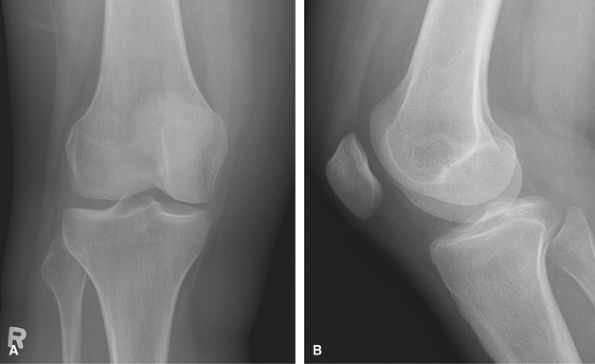

Trauma, Acute Injury

Shoot through lateral added to assess for a

lipohemarthrosis, if present a fracture must be sought. CT is a useful

adjunct to assess for occult tibial plateau fractures and to plan

surgery with fractures seen on radiographs. MRI being used increasingly

to assess accompanying soft tissue injuries in cases of tibial plateau

fractures.

![]() |

|

Figure 29 (A) AP. (B) Mediolateral lateral. (C) Lateromedial crosstable lateral.